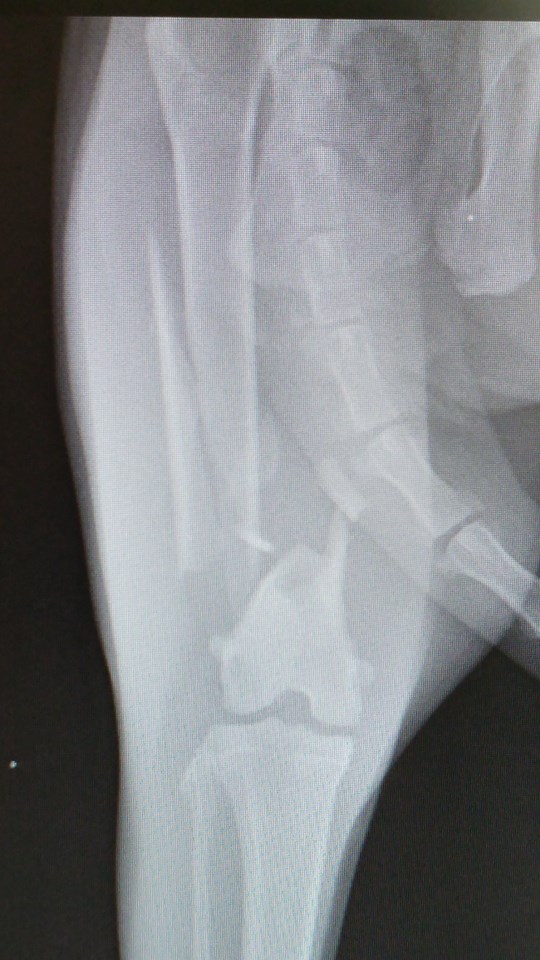

'זילולה' נעלמה ליותר משבוע וחזרה כשהיא לא דורכת על רגלה האחורית. בבדיקה וצילום במרפאה התגלה ש'זילולה' כנראה נדרסה ושברה שבר נוראי את רגלה. היא כנראה שברה את רגלה ביום שנעלמה, מאחר והשבר כבר לא היה "טרי", מה שסיבך מאוד את הטיפול בה. ואם לא די בכך, התקציב הטיפולי של 'זילולה' היה מוגבל ולא איפשר תיקון אורטופדי מתקדם.

כדי להציל את הרגל שלה, ביצענו ניתוח אורטופדי הרואי ומורכב, בו הצלחנו להחזיר את העצמות למנח כמעט אנטומי. וזאת כנגד כל הסיכויים כי השבר כבר התחיל בתהליך איחוי.